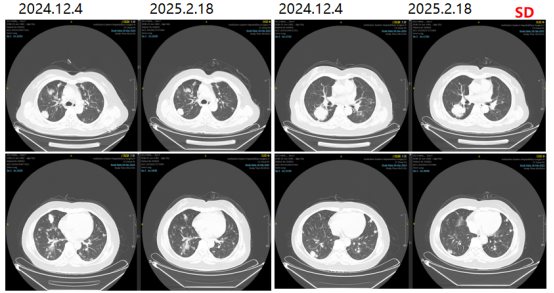

2024-12-04复查胸部CT提示两肺多发转移瘤,较前进展。

图10影像学复查结果

第七阶段治疗

更换治疗方案为TAS102+贝伐珠单抗方案。2024-12-05、2024-12-27、2025-01-07

分别予TAS102+贝伐珠单抗治疗。

图11影像学复查结果

2025-11-09复查胸部CT提示较前变化不明显。